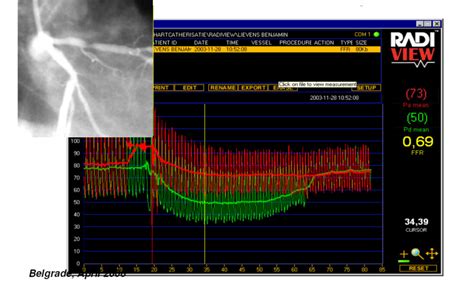

Alright, so what exactly is FFR? Imagine your coronary arteries are like highways, delivering vital blood to your heart. Sometimes, these highways get a bit congested due to blockages caused by plaque buildup (atherosclerosis). FFR indication helps us figure out just how congested they are, and whether it’s causing a problem. FFR measures the pressure difference across a blockage. To do this, your cardiologist will use a special wire that goes into the artery. This wire measures the pressure before and after the narrowed section. Then, the doctor gives you a drug that makes your heart pump as hard as it can (don’t worry, it’s safe!). The wire takes new measurements under these conditions, helping to see how much the blockage is limiting blood flow. The result is a number, the FFR value, that tells the doc how much the blockage is affecting blood flow. This gives a clear picture about what’s going on. This method is way more reliable than just looking at an angiogram (an X-ray of your arteries) alone. A healthy FFR is typically close to 1.0, and the lower the number, the more significant the blockage. When the FFR is below a certain threshold (usually 0.80), that’s when intervention is often recommended. This is all part of the FFR indication process.